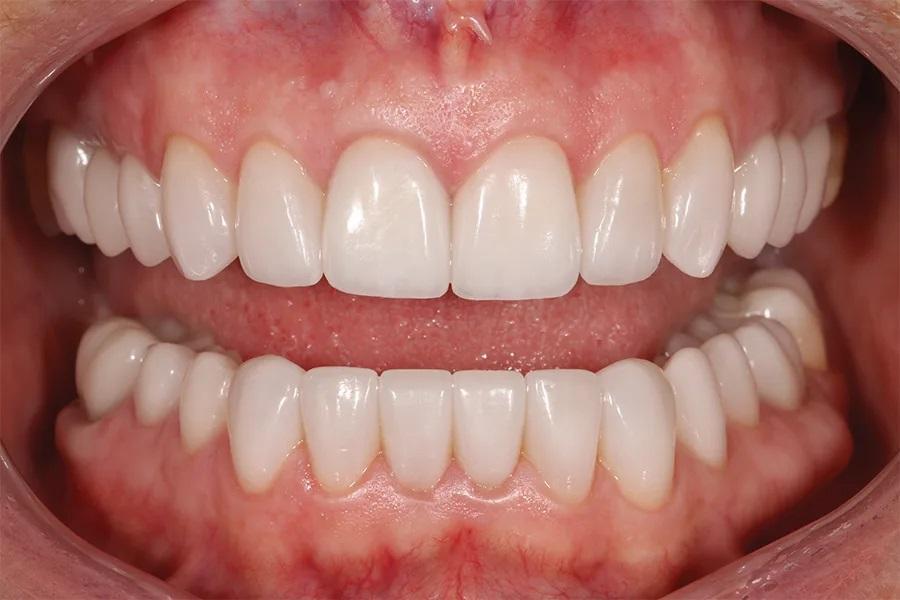

Разделение лечения на этапы в течение 18 месяцев позволило пациентке пройти полную реабилитацию полости рта без значительной одномоментной финансовой нагрузки. Результат превзошел ожидания пациентки, и она была полностью удовлетворена своей новой улыбкой (фото 12–16). При контрольном осмотре через 6 месяцев все реставрации оставались интактными, без сколов и разрушений, при этом пациентка отмечала комфортную окклюзию.

Фото 13. Крупный план улыбки после лечения, демонстрирующий целостность и согласованность реставраций, улучшающих общий вид улыбки.